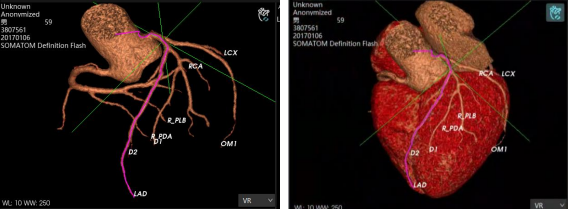

AI智能影像輔助診斷技術(shù)具有對醫(yī)學(xué)影像進行圖像篩查、病灶分類、定位、檢測、圖像分割等優(yōu)勢。它能夠在海量的醫(yī)學(xué)影像中準(zhǔn)確、快速且客觀地篩選出特定疾病的影像,確定圖像中病變區(qū)域的空間位置,檢測需要識別圖像中所有的目標(biāo)并且確定其類別,并在醫(yī)學(xué)影像中分割標(biāo)注出不同的組織和器官,計算圖像中的血流量等代謝信息。

除上述肺結(jié)節(jié)人工智能篩查示例外,目前已形成了全鏈路人工智能產(chǎn)品解決方案,在影像、超聲、病理方面都與AI智能影像輔助診斷技術(shù)高效結(jié)合,幫助醫(yī)院實現(xiàn)自動化、高精度的影像診斷檢查,讓患者在疾病篩查中實現(xiàn)早期診斷、預(yù)測、治療、療效評估與監(jiān)測。